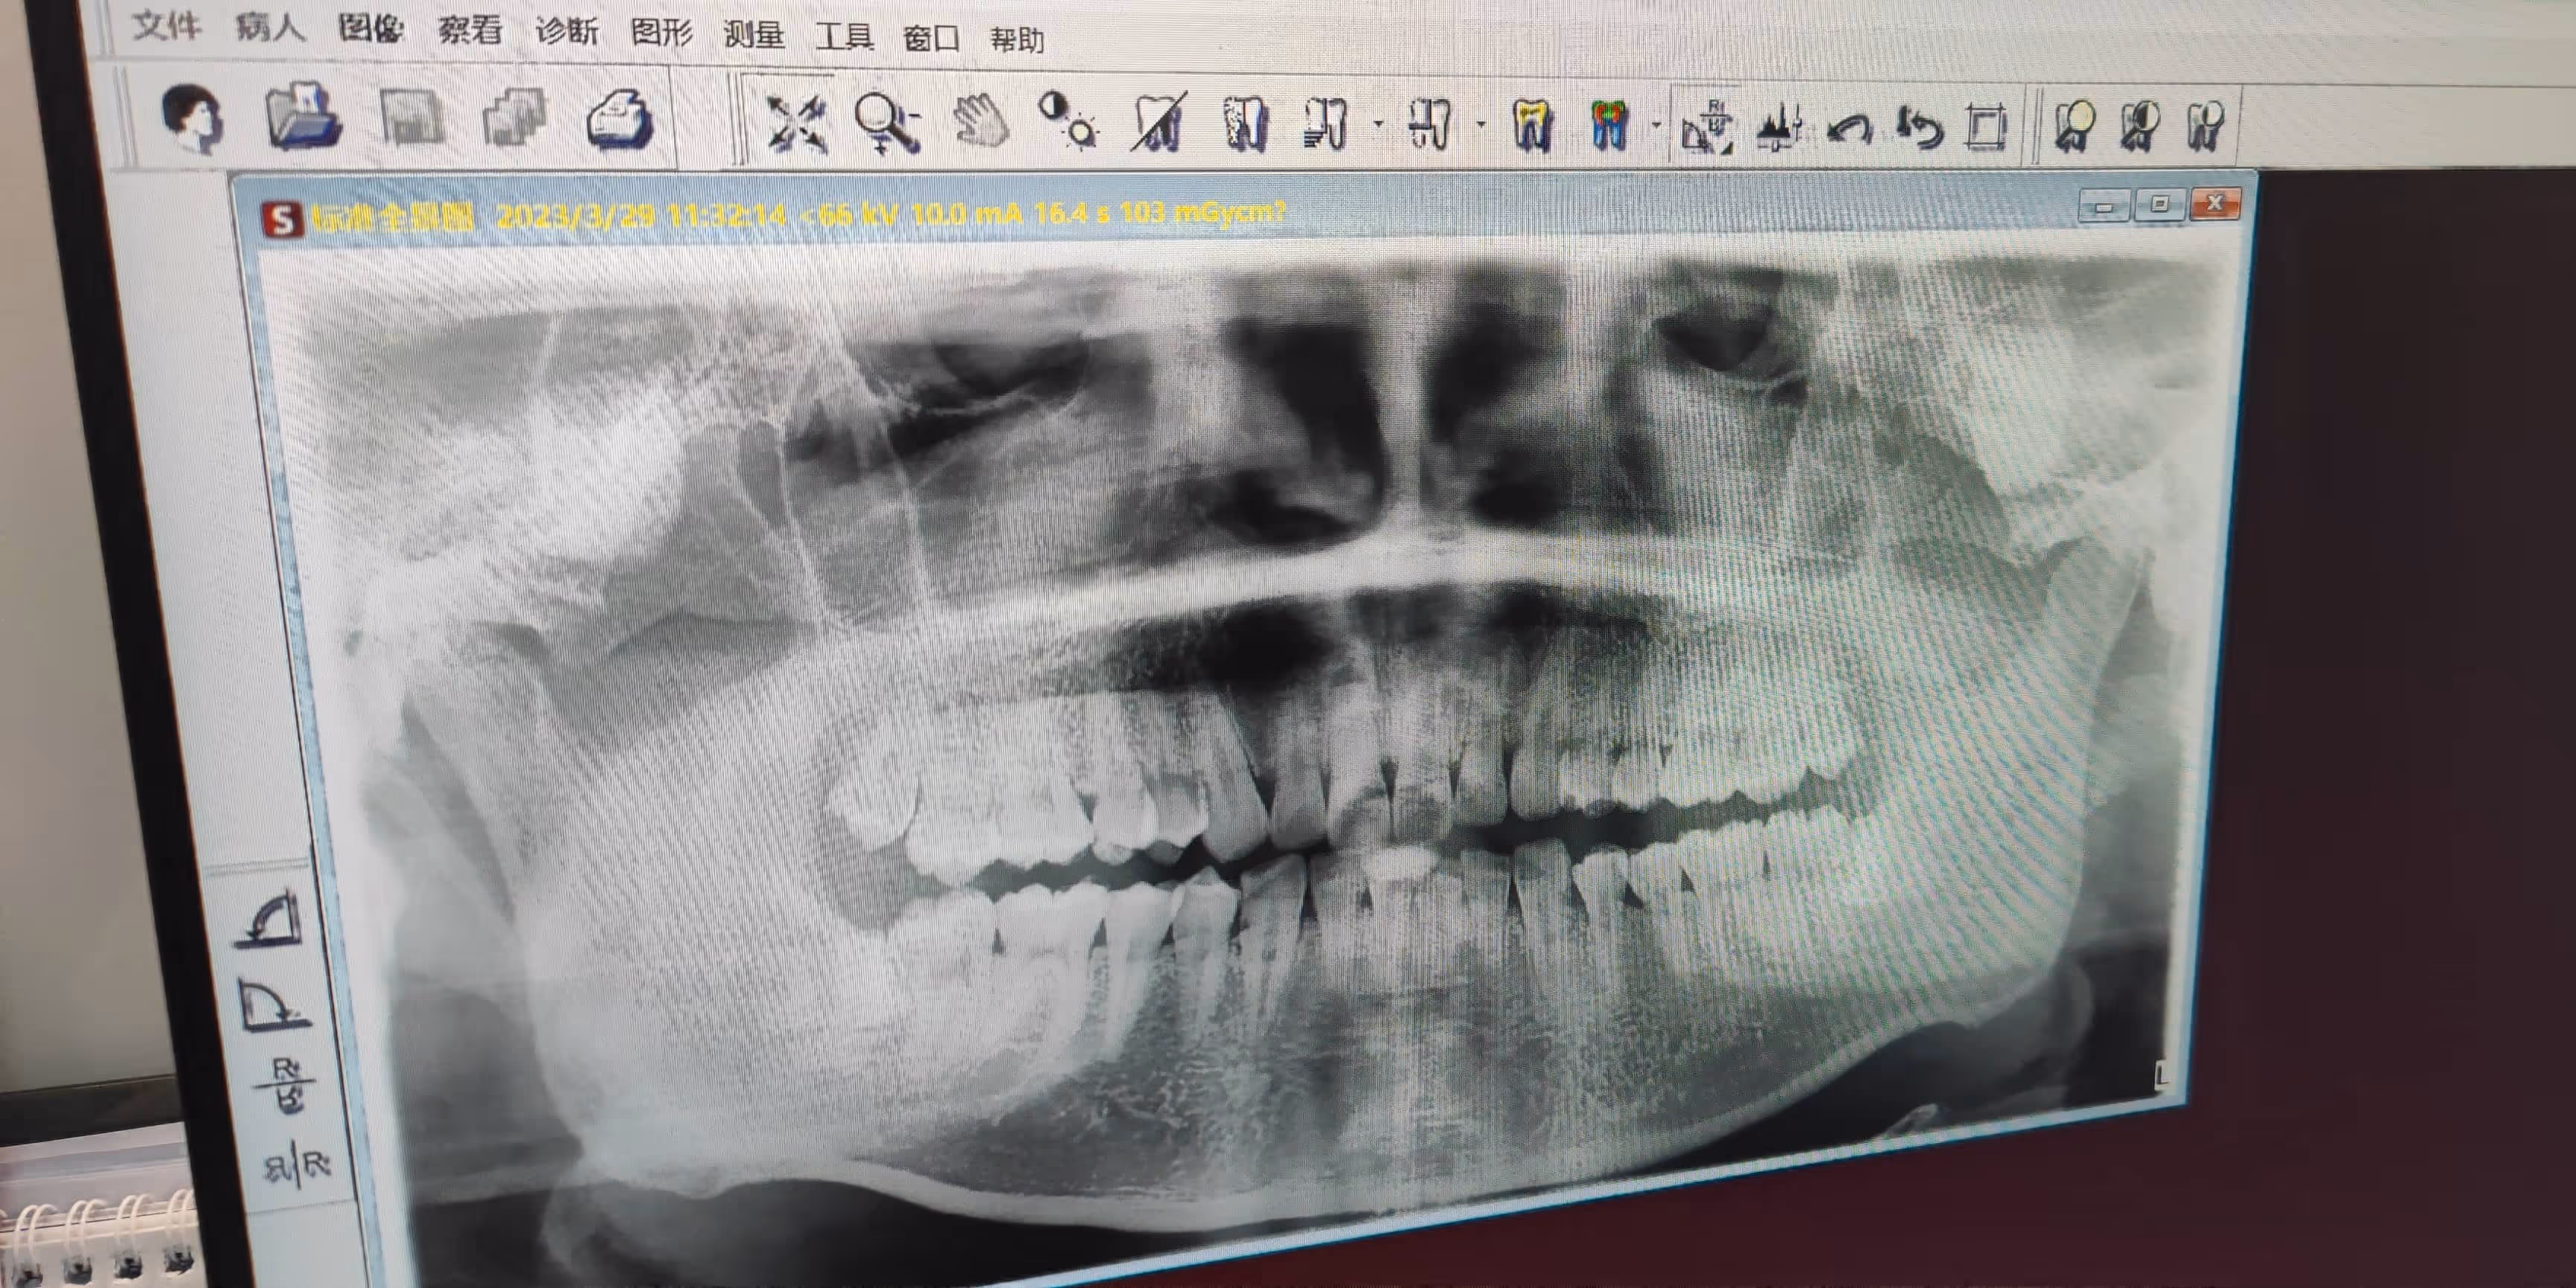

如图所示,俺的上牙智齿长的倒是很标准,但下牙偏偏是阻生智齿了。此次拔牙目标为上牙智齿,医生反正明确告知如果拔下压绝对会肿,祈祷它暂时不出问题吧,这次还不需要处理它。

虽然不是公立医院,但体验上似乎反而更好了?进门递水,确认要拔牙后先带你做 X 光检查(头一次穿厚厚的铅板服),接着量血压,吃止疼药,打麻药拔牙,结束后给冰袋止疼,同时咬棉球停留半小时观察,离开前加微信告之注意事项,最后三天后还有个回访询问。